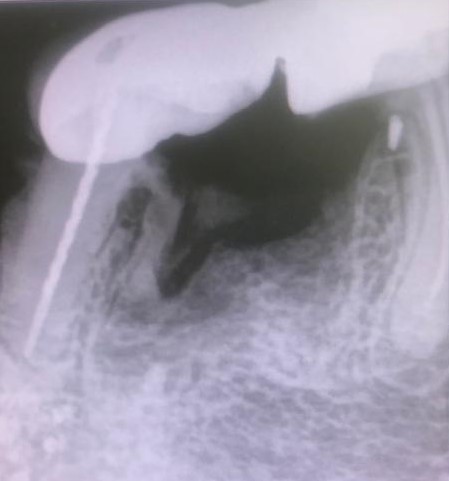

Presentamos un nuevo caso en el que la paciente presenta un gran dolor en su prótesis antigua (15 años) sobre dientes naturales tallados en zona inferior de molares. Es una paciente muy bruxómana, se unieron dos molares tallados con dos coronas. En el caso que presentamos el molar anterior estaba endodonciado ya antes de colocar la prótesis fija, pero el molar distal no. Y éste era la causa del gran dolor. Esto es por haberse filtrado creando caries y destrucción dentaria que llegaba al nervio. En conclusión, produciendo una gran pulpitis.

Esto provocaba en la paciente un gran dolor, pero ella no contemplaba en ese momento la opción de levantar la prótesis para explorar las piezas que había debajo, poder visualizar la destrucción dental y rehacer todo con una prótesis nueva. Por tanto, para quitar el dolor normalmente habría que haber hecho las extracciones de los dos molares, lo cual sería muy invalidante. En la clínica decidimos hacer una endodoncia de la raíz distal del último molar a través de la prótesis por la zona oclusal, y hacer odontosecciones de las raíces lesionadas sin quitar la prótesis. Ésta va permanecer tal como estaba.

Lo cierto es que las raíces  ya estaban bastante separadas de el resto de los molares correspondientes por su destrucción, lo que nos permitió la extracción de estas raíces en concreto. Teniendo en cuenta también que las raíces mesial y distal de cada molar no estaban unidas entre sí, sino que había una separación entre ellas.

La técnica quirúrgica para este menester es parecida a una apicectomía, pero en lugar de quitar solo el ápice radicular quitamos toda la raíz dental. Así pues lo que se hizo fue extracción de la raíz distal del primer molar y extracción de la raíz mesial del segundo molar. Con lo que la prótesis sigue teniendo dos pilares.

Con la secuencia de imágenes se comprende muy bien la técnica quirúrgica realizada.